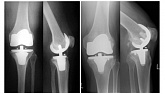

Еndoprosthesis of knee joint

In the late stages of arthrosis of the knee joint, accompanied by a pronounced restriction of the volume of movements, constant intense pain, deformity of the limb, the only way to recover is to replace the affected joint with an artificial joint - arthroplasty.

This method allows you to return the correct form of the limb, the full volume of movements in the joint, relieve the constant pain and crunch during movements and, as a result, significantly improve the patient's quality of life.

Below are presented X-ray photographs and photographs, illustrating the amount of motion in the affected joint before and after surgery.